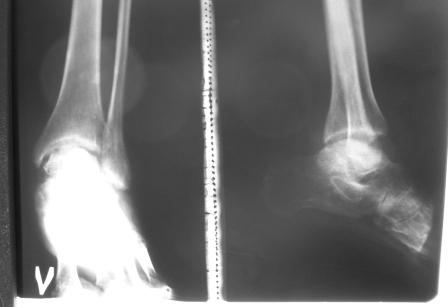

мои снимки

Кликните для загрузки файла Копия P1000367.JPG

А.Романова 14 Октябрь 2012, 12:53

Посмотрите, пожалуйста, мои снимки.